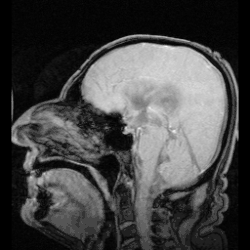

![]() The cerebrospinal fluid circulates in the subarachnoid space around the brain and spinal cord, and in the ventricles of the brain. | |

In humans, there is about 125–150 mL of CSF at any one time.[3] This CSF circulates within the ventricular system of the brain. The ventricles are a series of cavities filled with CSF. The majority of CSF is produced from within the two lateral ventricles. From here, CSF passes through the interventricular foramina to the third ventricle, then the cerebral aqueduct to the fourth ventricle. From the fourth ventricle, the fluid passes into the subarachnoid space through four openings – the central canal of the spinal cord, the median aperture, and the two lateral apertures.[3] CSF is present within the subarachnoid space, which covers the brain and spinal cord, and stretches below the end of the spinal cord to the sacrum.[3][4] There is a connection from the subarachnoid space to the bony labyrinth of the inner ear making the cerebrospinal fluid continuous with the perilymph in 93% of people.[5]